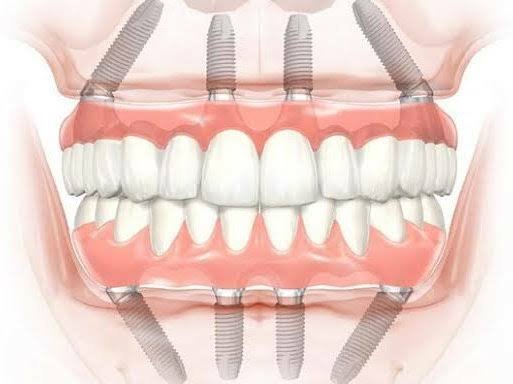

Burute Dental Clinic is the best dental clinic in Pimpri Chinchwad (PCMC) Pune, led by Dr. Mrunal Burute and Dr. Madhura Burute, expert implant dentists. We specialize in dental implants, full mouth dental implants, all-on-4, all-on-6, all-on-X implants, single tooth implants, immediate dental implants, and complex dental implant cases with high success rates. Known as a top dental implant clinic near me, we treat failed implants, severe bone loss, and advanced full mouth rehabilitation cases with precision. Our dental care services include root canal treatment, painless RCT, teeth whitening, aligners, braces, pediatric dental care, cosmetic dentistry, and complete oral care. If you are searching for dental implants near me visit us